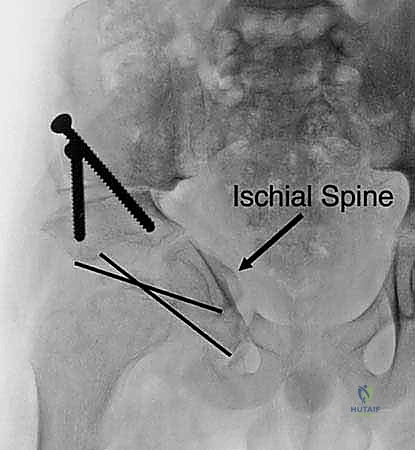

هنا تكمن عبقرية الإجراء. يتم استخدام مناشير جراحية دقيقة لعمل قطوع في:

* عظم الإسك (Ischium): العظم السفلي الخلفي للحوض.

* عظم العانة (Pubis): العظم الأمامي للحوض.

* عظم الحرقفة (Ilium): العظم العلوي العريض للحوض.

بمجرد اكتمال هذه القطوع الثلاثة، يصبح التجويف الحقي (الكوب) منفصلاً تماماً عن بقية الحوض، مع بقاء إمداداته الدموية سليمة.

4. إعادة التوجيه والتدوير (Rotation & Redirection)

باستخدام أدوات خاصة، يقوم الدكتور هطيف بتدوير التجويف الحقي الحر في ثلاثة أبعاد (للأمام، وللخارج، وللأسفل) حتى يغطي رأس عظم الفخذ بشكل مثالي وميكانيكي سليم. يتم التحقق من الزاوية الجديدة فوراً داخل غرفة العمليات باستخدام جهاز الأشعة السينية المتحرك (C-arm).